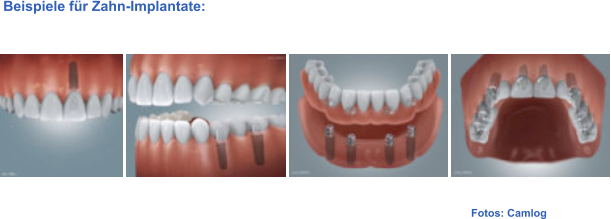

Fotos: Camlog  Beispiele für Zahn-Implantate: Implantate Implantate Knochenaufbau Knochenaufbau Sinuslift Sinuslift Video Implantation Video Implantation Video Implantation Video Implantation

Fotos: Camlog  Beispiele für Zahn-Implantate: